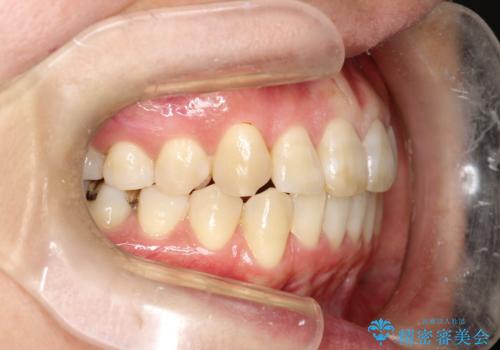

マウスピース枚数 初回52枚 + 追加19枚 + 追加12枚

概ね2年での治療完了となりました。

上の歯列に後方への力をかけるために、患者様には顎間ゴムをマウスピースと共に併用してもらいました。

当院独自の工夫を随所に盛り込み、狙い通りの治療結果が得られました。